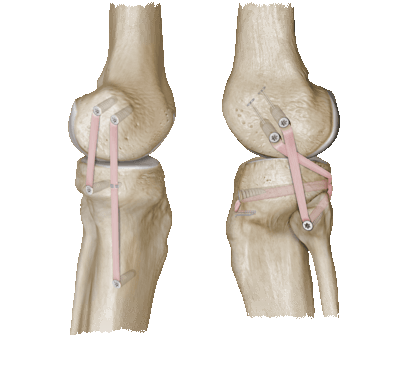

Хирургическое вмешательство подразумевает сшивание разорванных концов связки с помощью специальной медицинской нити. Если произошел разрыв связки на месте ее крепления к надколеннику, на его поверхности делается несколько неглубоких борозд, через которые протягиваются нити. Для укрепления места соединения связки накладывается дополнительный шов. Все манипуляции проводятся не рассасывающейся нитью.

При сложных клинических случаях, когда связка порвана таким образом, что нет возможности сшить ее концы, перед операцией требуется применение специальных втягивающих аппаратов, например, Илизарова. В случае формирования спаек проводится их разделение. Нередко сшить разорванные концы можно только путем наложения дополнительного лоскута ткани между ними. Такой имплант берется из биологических тканей человека, из куска ткани сухожилия.